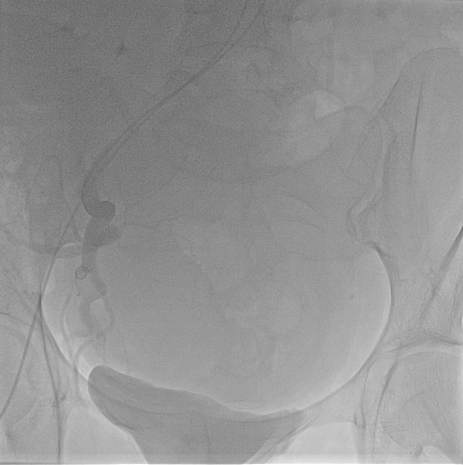

2014 թ. սեպտեմբերի15-ին «Էրեբունի» բժշկական կենտրոնում հերթական բացառիկ վիրահատությունն է անցկացվել՝ արգանդային զարկերակների էմբոլիզացիա՝ արգանդի միոմայի պատճառով: Այս էնդովասկուլյար միջամտությունը միոմայի բուժման արմատական մեթոդներից է:

2014 թ. սեպտեմբերի10-ին 52-ամյա Գ.Օ. «Էրեբունի» բժշկական կենտրոն դիմեց արգանդի միոմա, մետրոռագիա, լյարդի աջ մասի հսկայական հեմանգիոմա ախտորոշմամբ: Հիվանդի վիճակը ծանր էր, անընդմեջ արյունահոսության պատճառով նրա մոտ զարգացել էր նաև սակավարյունություն: Հիվանդին կրկնակի արյան փոխներարկում էր իրականացվել, ինչից հետո միայն հնարավոր էր դարձել վիրահատության իրականացումը:

Հիվանդին հակացուցված էր բաց վիրահատության ճանապարհով արգանդի հեռացում իրականացնել, քանի որ վիրահատության ընթացքում հեմանգիոմայի վնասման ռիսկը մեծ էր, ինչն իր հերթին կարող էր զանգվածային արյունահոսության պատճառ լիներ:

Վիրահատության տևողությունը 30-40 րոպե է: Վիրահատության էությունը երկու արգանդային զարկերակների էմբոլիզացիա կատարելն է՝ չխախտելով արյան շրջանառությունն արգանդում: Այն նվազագույն միջամտություն պահանջող և քիչ վնասվածքներ հարուցող վիրահատություն է, որն իրականացվում է տեղային անզգայացմամբ: Վիրահատությունը հնարավորություն է ընձեռում խուսափել հիստեէկտոմիայից (արգանդի հեռացումից), առավել ևս, երբ կինը դեռ վերարտադրողական տարիքում է գտնվում: Այսպիսի վիրահատություններ կարելի է անցկացնել ինչպես եզակի միոմայի, այնպես էլ ցանկացած տեղայնացման արգանդի միոմատոզի ժամանակ:

Վիրահատությունն անց է կացվել փորձառու ինվազիվ սրտաբան Արսեն Ծատուրյանի կողմից, ով բազմիցս իրականացրել է վերոնշյալից ոչ պակաս բարդ վիրահատություններ և որոնց դրական արդյունքները խոսում են նրա պրոֆեսիոնալիզմի մասին:

Հետվիրահատական շրջանն անցել է հարթ՝ առանց բարդությունների: Հիվանդը երկու օր գտնվել է շուրջօրյա հսկողության տակ, այնուհետև դուրս է գրվել՝ շարունակելով մնալ բժիշկների ուշադրության կենտրոնում:

Անհրաժեշտ է նշել, որ այսպիսի վիրահատություն Հայաստանում առաջին անգամ է իրականացվել: